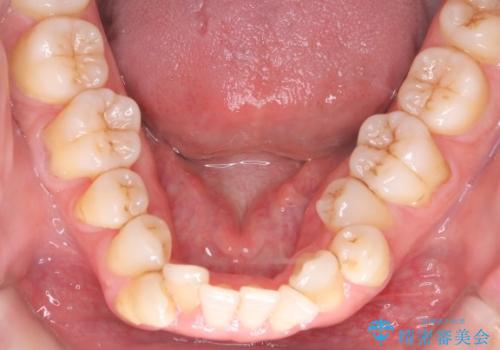

- 治療計画

叢生量が大きいため、上下顎両側4番を抜歯しました。矯正治療による歯肉退縮の著しい悪化もなく、主訴であるガタつきも改善できました。